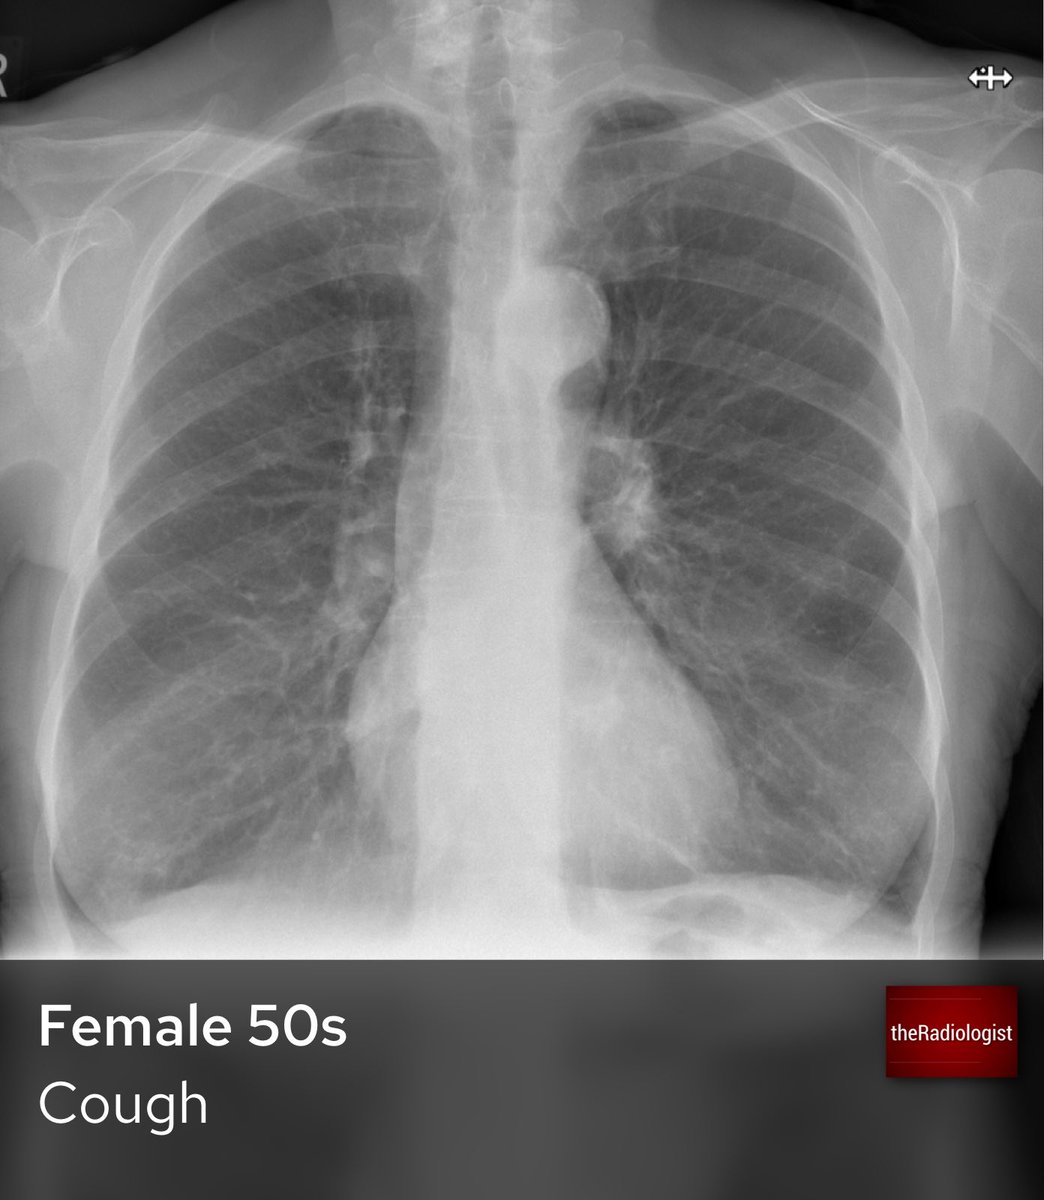

Charles Milrod, MD (@charlesmilrod) 's Twitter Profile Photo

Picture this: Your patient with myeloma presents with hypercalcemia. You find this 👇 on your evaluation. How (and why) is this an emergency? 🤔 A #tweetorial 🧵 1/7

Picture this:

Your patient with myeloma presents with hypercalcemia.

You find this 👇 on your evaluation.

How (and why) is this an emergency? 🤔

A #tweetorial 🧵 1/7